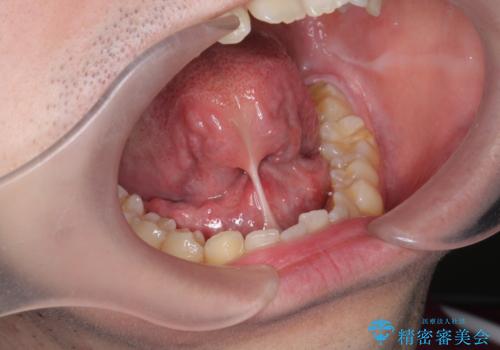

PMTC(歯科医院での専門的なクリーニング)

歯の着色だけでなく、汚れも除去し歯の表面がツルツルになったと喜んでいただけました。